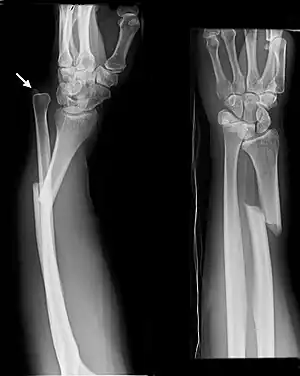

The diagnosis of a forearm fracture is made by first inspecting and then feeling the injured forearm for any obvious deformity and tenderness, with particular attention to the radial head.[2] The type of forearm fracture can be confirmed by an x-ray, usually with views from the front and the side, and must include the wrist and elbow joints.[2]

-

Front view of displaced fractured radius and ulna at wrist -

Side view of displaced fractured radius and ulna at wrist -

Front view of bowing fractured radius and ulna -

Side view of bowing fractured radius and ulna